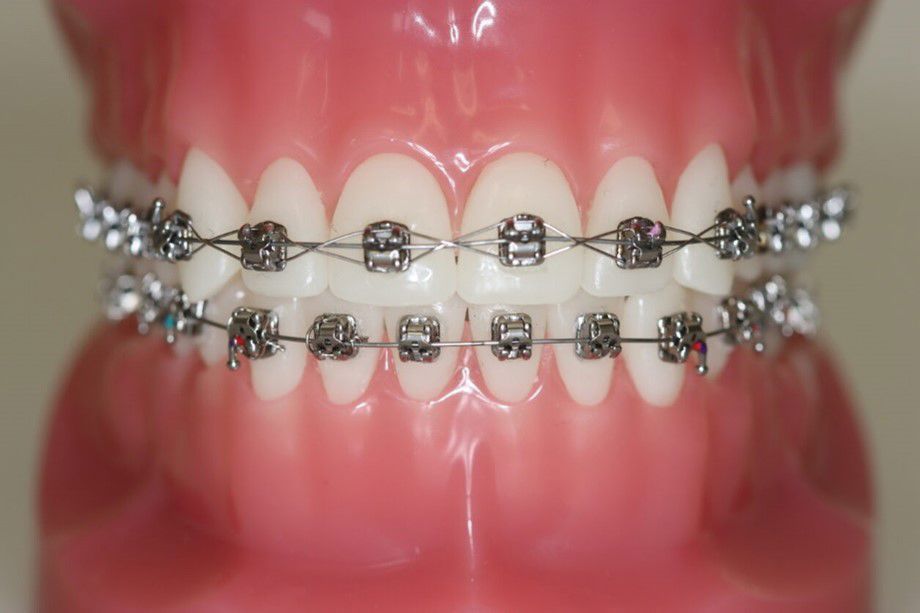

Brackets eller ”togskinner” bliver limet fast på tænderne. Oftest er det nødvendigt med fastsiddende bøjler i både overkæben og underkæben.

Det kan tage op til en uge at vænne sig til faste bøjler eller "brackets". Tænderne vil være ømme de første 2-3 dage, og det kan være rart med mad, der ikke skal tygges for meget.

I starten kan der opstå en lille blæne eller et lille sår i slimhinden. Du får voks med hjem til at sætte på dine bøjler.

For at undgå at bøjlen går i stykker eller bliver løs, er det vigtigt, at du ikke spiser hårde og seje fødevarer som f. eks. karameller, vingummi, lakridser, bolsjer og slikkepinde.

Hårde madvarer som f.eks. gulerødder, æbler og pærer skæres i mindre stykker.

Det er vigtigt, at du børster tænder og bøjler grundigt rene morgen og aften. Ellers er der risiko for tandkødsbetændelse og skader på tænderne - eller i værste fald huller i tænderne.

Du får et tandbørstesæt udleveret sammen med en grundig instruktion, inden du forlader klinikken.